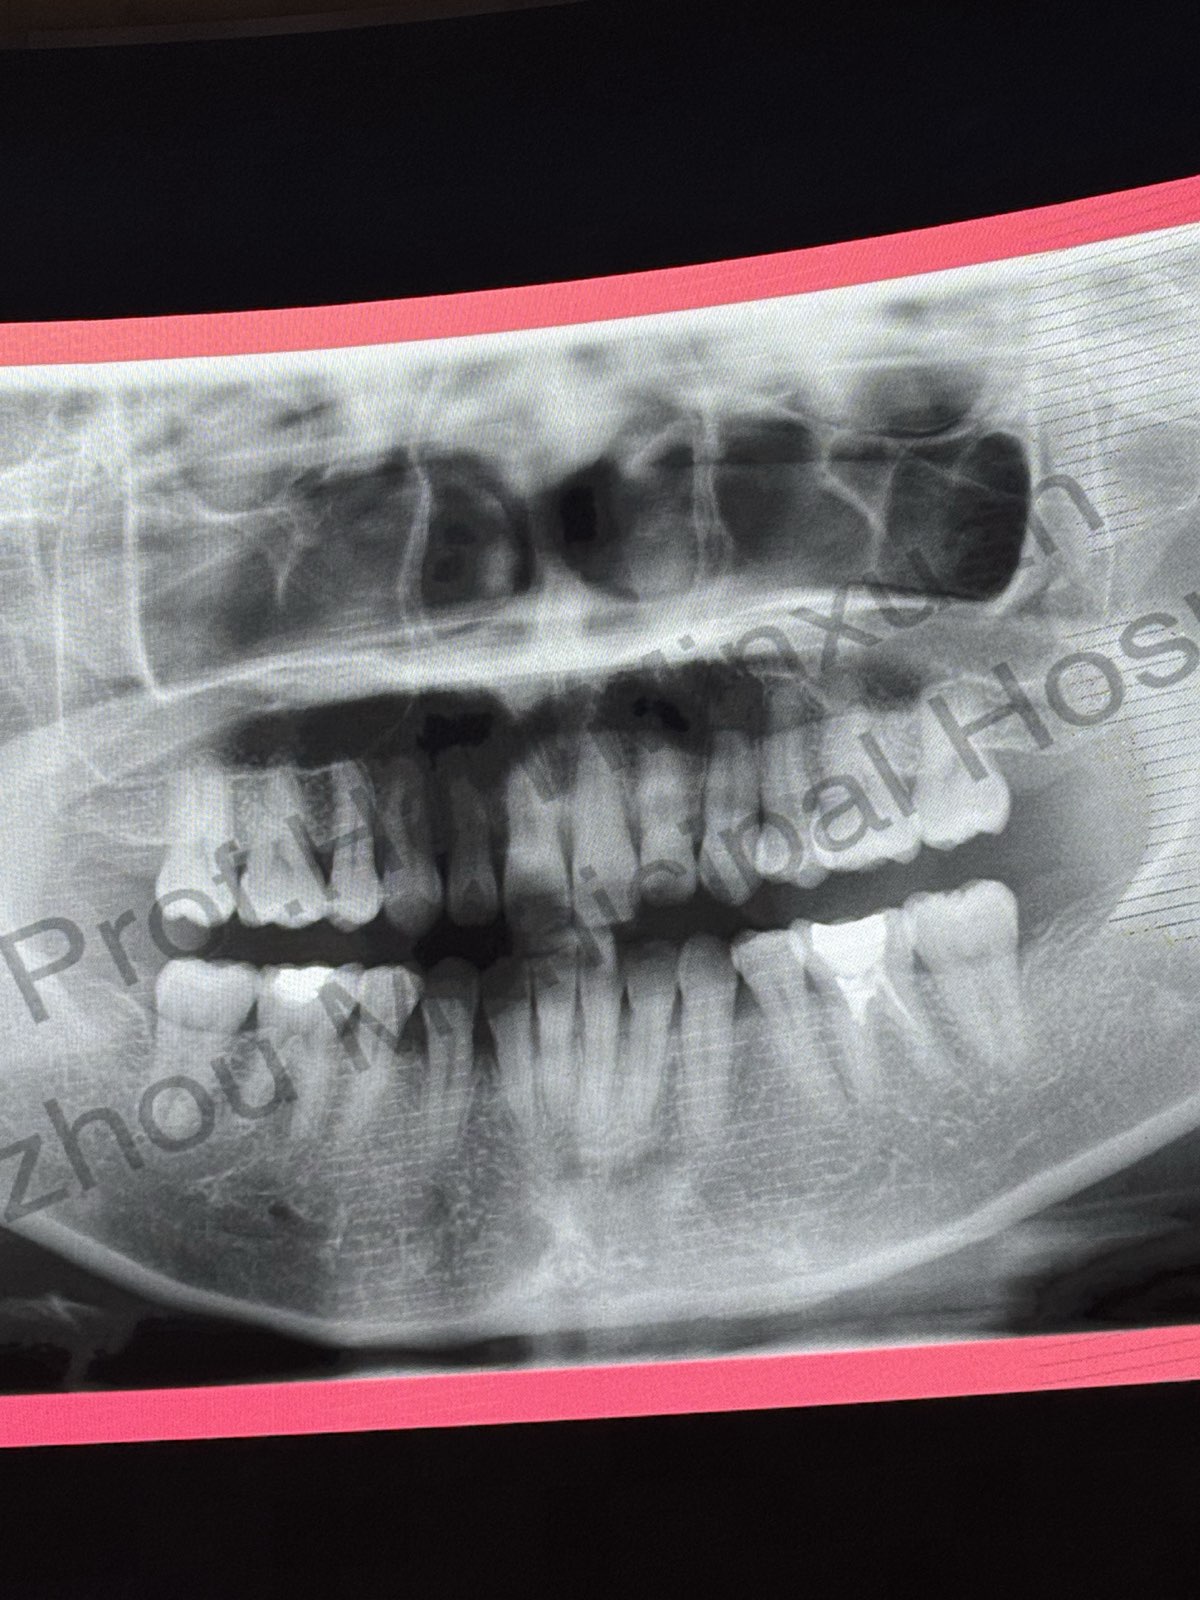

• パノラマレントゲン: 治療前の上顎前歯は骨のデヒッセンス(骨露出)やフェネストレーション(骨欠損窓)があることが多い。

• パノラマレントゲン: 歯周組織の状態も良好ではない。

• 術前パノラマレントゲン: 虫歯と修復歯(下顎第二大臼歯)が存在。